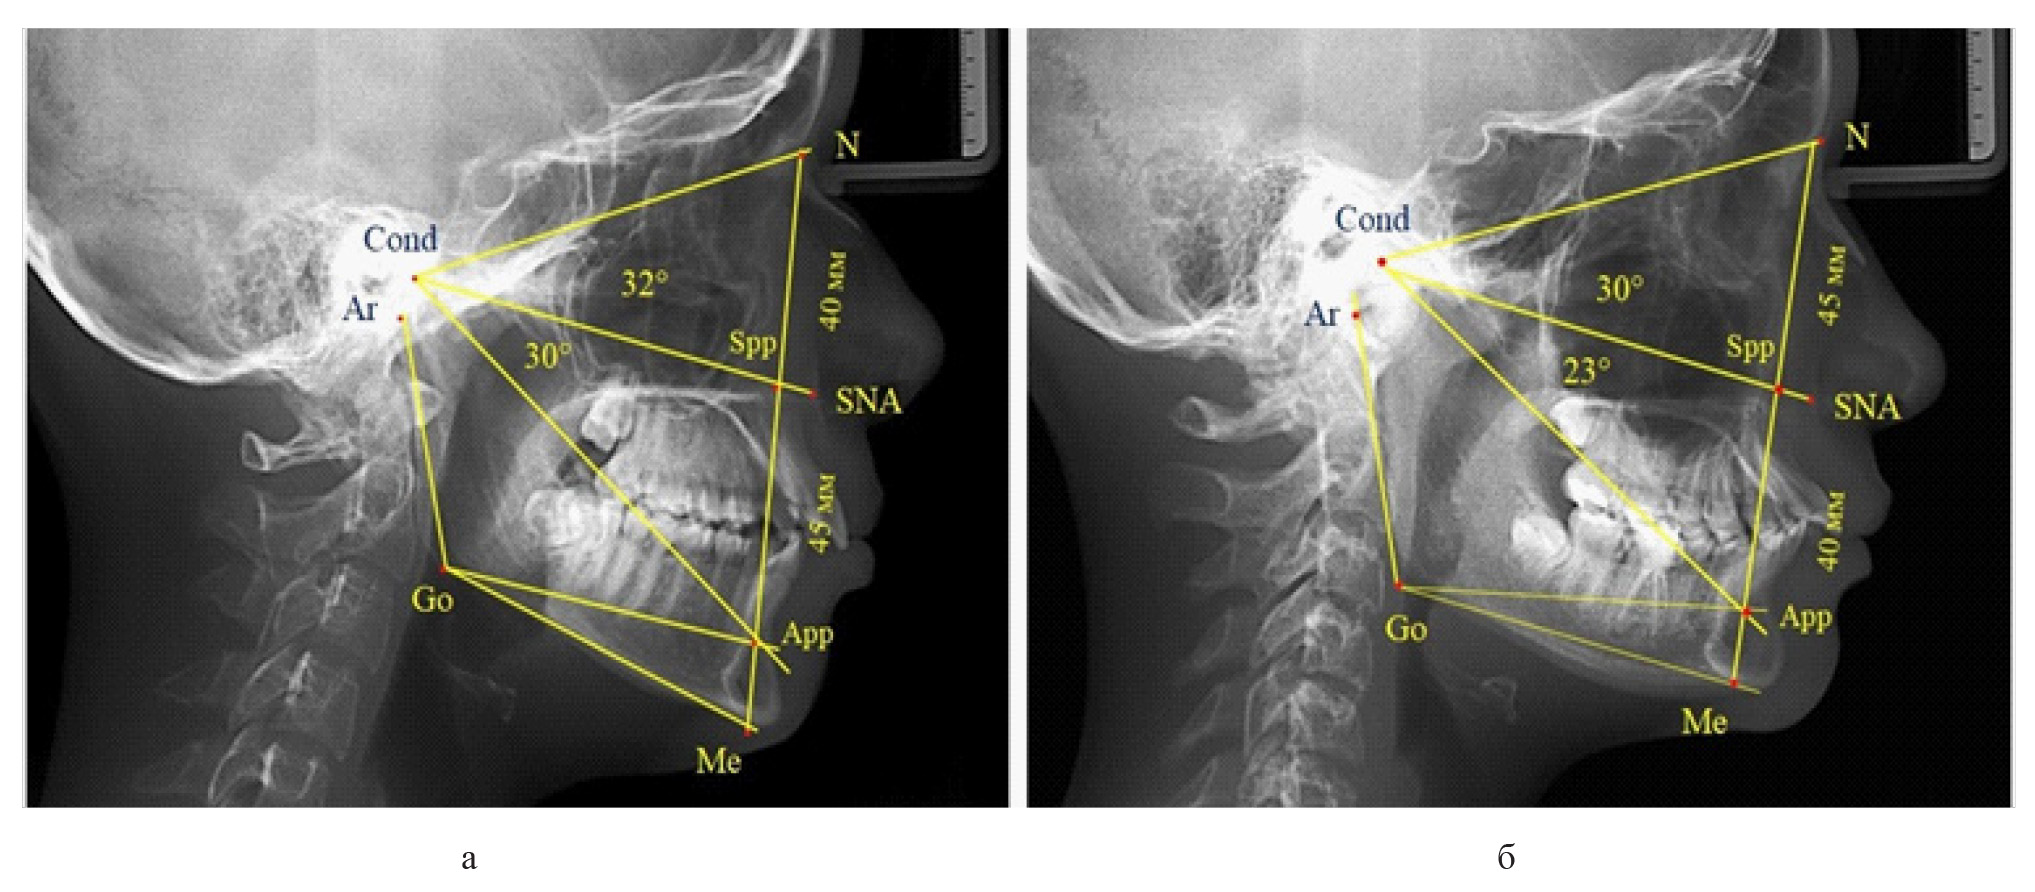

Признаки снижения высоты назального отдела вплоть до уровня горизонтального патологического типа при физиологической окклюзии были определены у 10 человек [(17,86 ± 5,11) %]. При этом параметры гнатического отдела соответствовали физиологической норме либо физиологическому горизонтальному типу (рис. 4).

Рис. 4. Варианты ТРГ с укороченными размерами носового отдела и оптимальными (а) и укороченными (б) размерами гнатической части